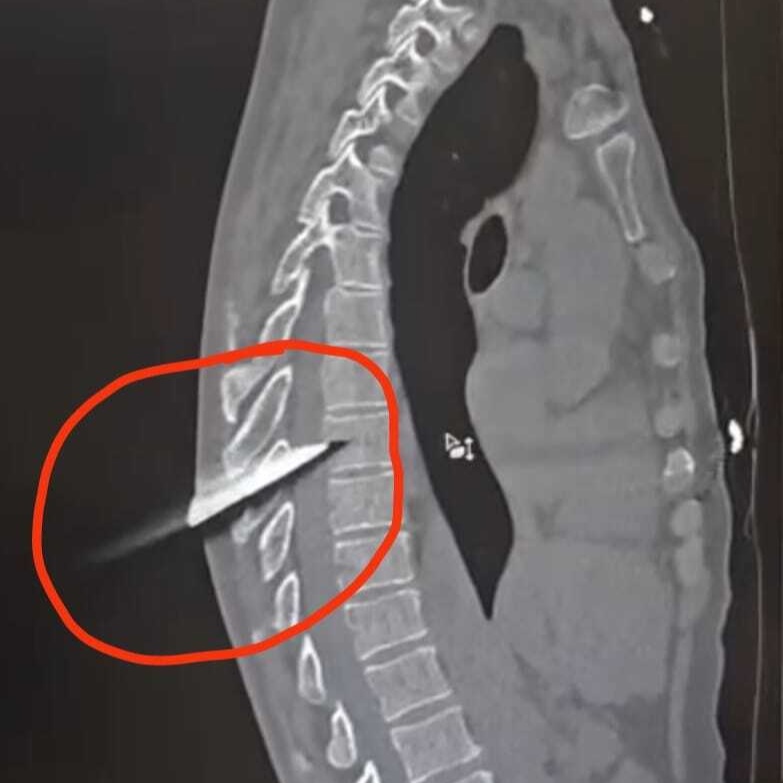

15-сантиметровое лезвие большого кухонного ножа повредило ткани, прошло между позвонков грудного отдела позвоночника и задело спинной мозг. Все это представляло угрозу для жизни, к тому же человек мог остаться парализованным.

Операционная бригада ГБСМП – врач-нейрохирург Клим Бухмиллер, анестезиолог Ирина Курапова, операционная медсестра Елена Головина, а в послеоперационном периоде лечащий врач Дмитрий Козаченко – совершили настоящее чудо. После ювелирной операции по извлечению инородного предмета и проведенного лечения, у мужчины полностью сохранены все двигательные функции, он самосточтельно ходит по палате и готовится к выписке.